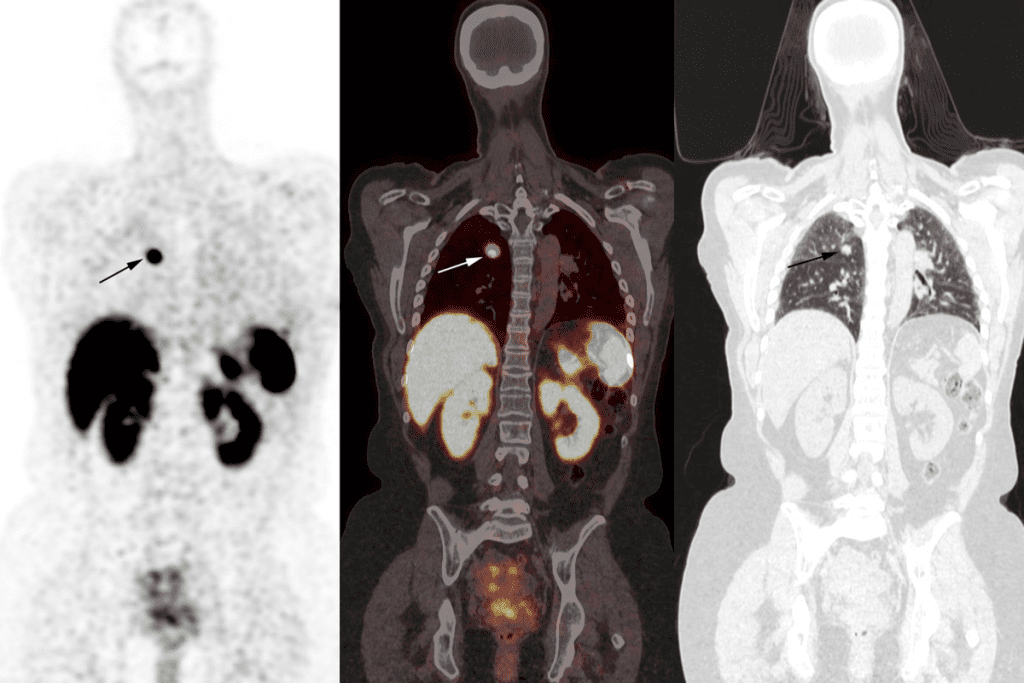

PET Scans for Bone Metastases

Positron Emission Tomography (PET) scans, like those with F-Fluorodeoxyglucose (FDG), are key for finding bone metastases. They combine functional and anatomical details, making them great for cancer staging.

The advantages of PET scans include:

- High sensitivity for detecting metabolically active cancer cells

- Ability to assess the entire body in a single scan

- Combining functional and anatomical information